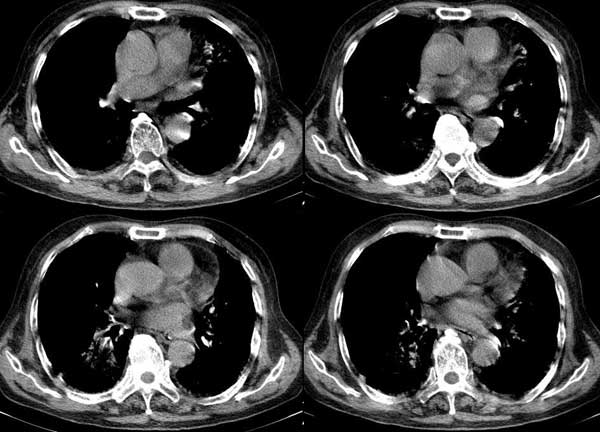

以下是引用dalianren在2006-7-20 21:23:00的发言:[br]我考虑是肺泡蛋白沉积症:典型表现为两肺内散在片状\"磨玻璃\"样混浊区呈地图样分布.

以下是引用lj0804在2006-7-21 12:57:00的发言:[br]支持[br]我考虑是肺泡蛋白沉积症:典型表现为两肺内散在片状\"磨玻璃\"样混浊去呈地图样分布.